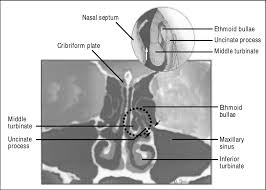

The openings in the cribriform plate comprises of nerves that enable humans to smell and differentiate between odors. It is a part of ethmoid bone and supports the olfactory bulb which lies in the olfactory fossa. Function in sinus system in sinus. The cribriform plate is best observed endocranially where the ethmoid can be seen to fill the ethmoid notch of the frontal.

In mammalian anatomy the cribriform plate horizontal lamina or lamina cribrosa of the ethmoid bone is received into the ethmoidal notch of the frontal bone and roofs in the nasal cavities. The foramina in the middle of the groove are small and allows the passing of the nerves to the roof of the nasal cavity. Paranasal air sinuses this bone the cribriform plate transmits the olfactory nerves that carry the sense of smell. It is used as a marker or guide for the silverware and other components of the place setting and functions as a service plate when the food is.

The cribriform plate less commonly also called the lamina cribrosa of the ethmoid bone is a sieve like structure between the anterior cranial fossa and the nasal cavity. The cribriform plate and crista galli are part. Function of cribriform plate the plate provides support to the olfactory bulb which is perforated by foramina to serve as a passage to the olfactory nerves. The cribriform plate is narrow with deep grooves supporting the olfactory bulb and is perforated by olfactory foramina allowing the passage of the olfactory nerves.

Axons from the olfactory receptor cells in the nasal cavity send projections into the olfactory bulb which bundles into cranial nerve i olfactory nerve.